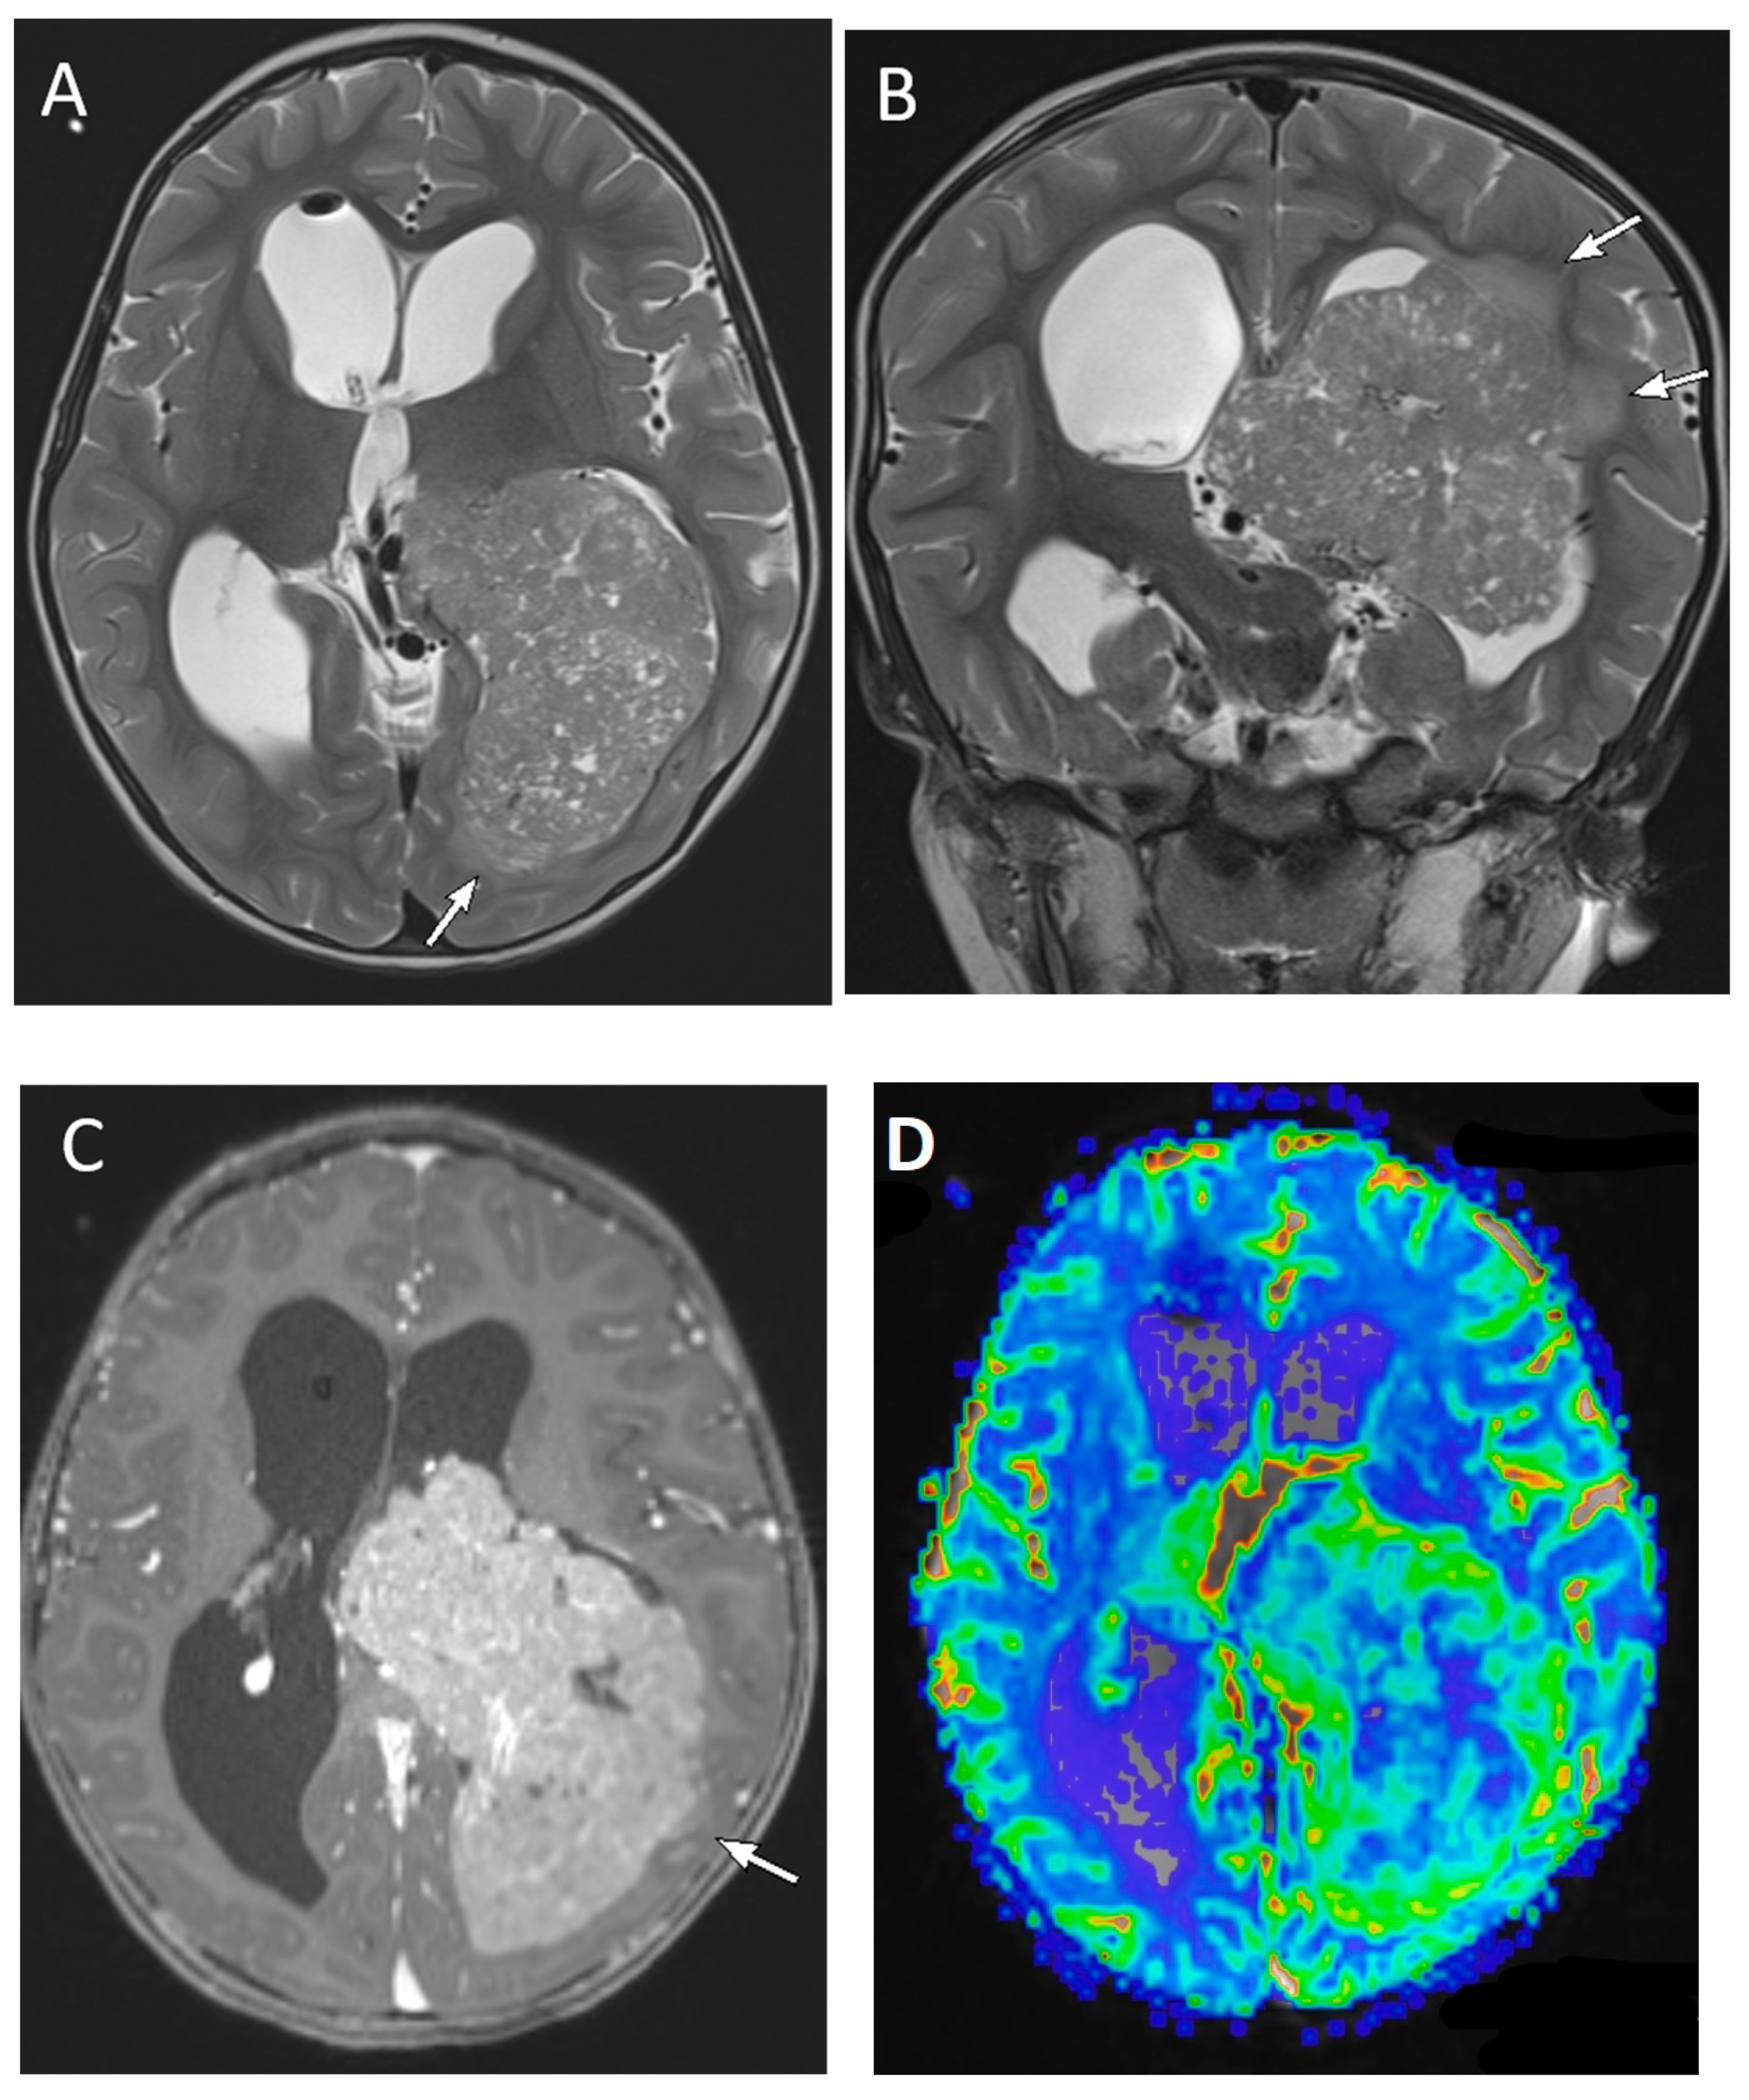

| Medulloblastoma | Exclusively posterior fossa Most commonly in fourth ventricle/cerebellar vermis (non-WNT, non-SHH, or WNT), can involve cerebellopontine angle (WNT) or cerebellar hemispheres with extra-axial extension (SHH) | Diffusion restricting Variable enhancement Cystic/necrotic change may be present Calcifications uncommon Taurine peak characteristic |

| Atypical teratoid/rhabdoid tumor | Posterior fossa (slightly more common) or cerebral hemispheres May be extra-axial | Diffusion restricting Enhancement usually present More heterogenous than medulloblastomas, with cysts/necrosis, calcification, and hemorrhage |